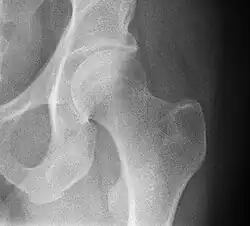

Mediale Schenkelhalsfraktur ohne Dislokation -

Laterale Schenkelhalsfraktur mit Adduktions-Dislokation -

Im Vergleich dazu ein gesundes Hüftgelenk